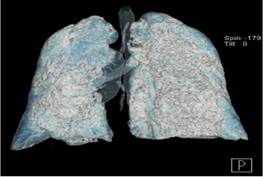

Debido a la sobreexigencia de los servicios médicos y laboratoriales por aquel momento, no se tiene confirmación positiva de la RT-PCR SARS-CoV-2 hasta los 3 días de su admisión intrahospitalaria. Se toman nuevas analíticas de control y en éstas se aprecia notable aumento del dímero-D llegando hasta los 4 360 ng/ml (Ver Tabla. 1). En el contexto de un paciente con progresiva escalación de las medidas ventilatorias con cánulas nasales de alto flujo y bajo la utilización de los índices Rox y Kirby, aunado al aumento de la respuesta inflamatoria sistémica, se sospecha de tromboembolia pulmonar (TEP) versus alguna coinfección o sobreinfección por lo que se solicitan angiografía por tomografía computada (Angio-TC), TC-Tx de control y panel PCR respiratorio. En Angio-TC no se identifican datos sugerentes de TEP, TC-Tx muestra hallazgos compatibles con neumonía producida por SARS-CoV-2 en fase moderada, progresión de la infección en base a última toma de control, atelectasias y consolidaciones bilaterales hacia las bases (Ver Figura. 2 y 3). Panel PCR respiratorio revela la detección del virus Influenza A H1N1.

Este reporte de caso presentado destaca 2 desafíos en el diagnóstico y por lo tanto en el tratamiento conjunto de COVID-19 e Influenza A H1N1. Primero, aunque generalmente la toma de tomografía computada de tórax con el respectivo hallazgo de patrón en vidrio esmerilado junto a la sintomatología clásica de COVID-19 ya mencionada, son aceptables para establecer una sospecha diagnóstica, pueden ser insuficientes en caso de coinfección de Influenza A H1N1. Los hallazgos iniciales tomográficos de este caso no mostraron ningún signo que condujera a la sospecha de alguna coinfección o sobreinfección, ya que sólo mostraron patrón de vidrio esmerilado y empedrados postero-basales, signos característicos de infección por SARS-CoV-2. No fue hasta que el curso de la infección avanzó, y ante la falta de mejoría tanto clínica como analítica del paciente, que se realizó tomografía computada de tórax de control, la cual evidenció la aparición de consolidaciones bilaterales, un hallazgo recurrente en caso de infección por Influenza A H1N1. Por otro lado, una problemática más durante el diagnóstico; fueron las analíticas de sangre con los correspondientes reactantes de fase aguda quienes ante la presencia de ambas entidades patológicas no fueron de utilidad para poder distinguir si la enfermedad de base, en este caso COVID-19, se encontraba acompañada de alguna otra entidad patológica. Sino solo para evidenciar el incremento sostenido de los parámetros inflamatorios.